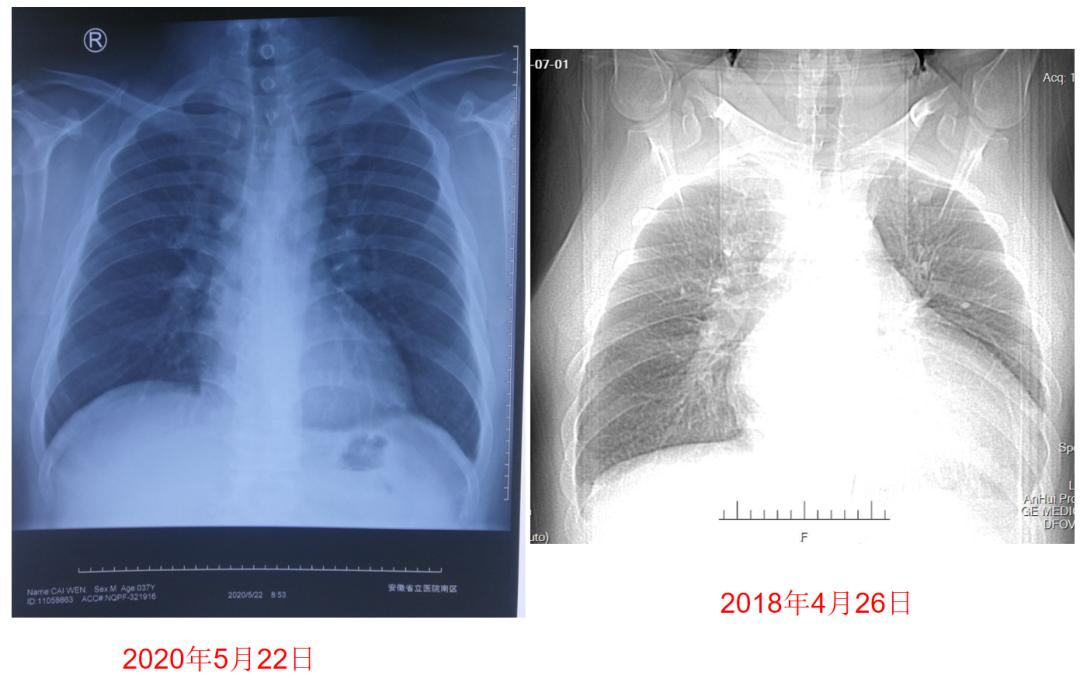

图5:患者药物治疗前后胸片检查对比

②出院后1年随访过程。出院后2月随访时,患者血压保持于100~130/60~80 mmHg,将沙库巴曲缬沙坦加量至100 mg bid,复查LVEF上升至37%。

用药1年后,左房内径(LA)、左室内径(LV)、右室内径(RV)、右房内径(RA)、肺动脉收缩压(SPAP)等心脏重构指标均明显改善,LVEF上升至52%(表2)。

③出院后2年随访。患者日常无活动后胸闷、气促,无夜间阵发性呼吸困难、能做家务、接送女儿上学,未再住院,通过适度运动结合节食,体重再次减轻25公斤,目前体重110公斤。出院后2年复查LVEF示53%,由于患者近12个月心脏彩超无明显变化,将沙库巴曲缬沙坦加量至200 mg bid,期待进一步改善。